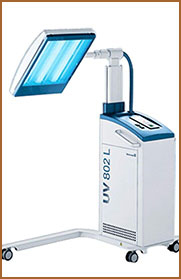

医用三痒

治疗仪

311窄谱UVB

治疗仪

智能中药熏蒸

治疗仪